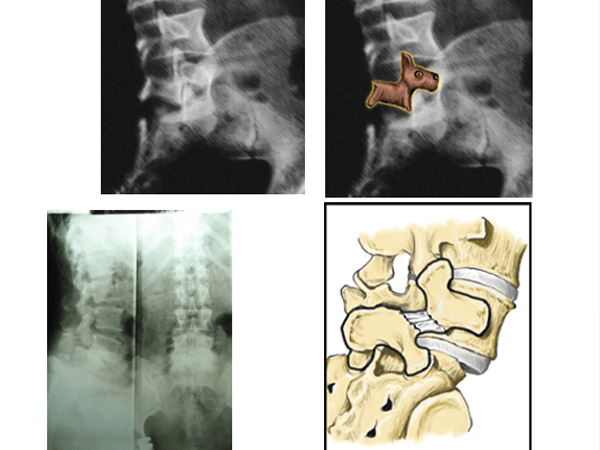

Cận lâm sàng: Đánh giá đặc điểm TĐS trên X-quang thẳng, nghiêng, chếch 3/4 trái- phải, nghiêng cúi – ưỡn tối đa. Đánh giá chiều cao đĩa đệm trước mổ, phân loại nguyên nhân TĐS, phân độ TĐS theo phân loại của Meyerding. MRI đánh giá hẹp ống sống hay lỗ liên hợp.

Thực thể: Dấu hiệu bậc thang là dấu hiệu biến dạng đặc trưng trong chẩn đoán lâm sàng TĐS. Tuy nhiên dấu hiệu này khó phát hiện ở những bệnh nhân trượt độ I và BN to béo. Nghiên cứu của chúng tôi gặp 10 BN (33,3%) có dấu hiệu bậc thang. Nghiên cứu của Nguyễn Vũ là 58,1%; Phan Trọng Hậu là 87%. Sở dĩ có sự khác biệt này do nghiên cứu của chúng tôi có độ trượt nhẹ (độ I) hơn so với các nghiên cứu của Nguyễn Vũ và Phan Trọng Hậu [1], [5].

Xquang: Trên phim Xquang cột sống thắt lưng có 93,3% BN bị TĐS do thoái hóa, chỉ có 2 BN (6,7%) bị TĐS do khuyết eo gặp ở bệnh nhân trẻ tuổi. Đánh giá mức độ TĐS theo Meyerding, trượt độ I chiếm 86,7%, còn lại độ II và độ III. Kết quả này tương đồng với một số nghiên cứu khác như: Phan Trọng Hậu trượt độ I là 51,4%, độ II là 41,4%, độ III là 7,2%; Phan Minh Đức có kết quả trượt độ I là 69%, độ II là 30%, độ III là 1%.

Cộng hưởng từ: Nghiên cứu của chúng tôi có 27 BN (90%) có hình ảnh hẹp ống sống. Nguyên nhân gây hẹp là do thân đốt sống trượt, đĩa đệm thoát vị, phì đại mấu khớp và dây chằng vàng do thoái hóa. Nghiên cứu của Phan Trọng Hậu cho kết quả hẹp ống sống trên CHT là 44,3%, nghiên cứu của Edelson gặp 32% [1]. Hẹp ống sống, lý do phổ biến cho phẫu thuật vùng thắt lưng ở người lớn trên 65 tuổi, bệnh nhân thường có biểu hiện đau cách hồi thần kinh, liên quan nhiều đến tư thế ngồi, đi lại và vận động. Hẹp lỗ liên hợp gây chèn ép rễ do di lệch trượt của thân đốt sống về phía trước và do giảm chiều cao đĩa đệm, ngoài ra mấu khớp phì đại gây nên. Trong nghiên cứu của chúng tôi hình ảnh hẹp lỗ liên hợp có 10% bệnh nhân. Như vậy có thể thấy hẹp lỗ liên hợp là một trong những nguyên nhân gây đau rễ thần kinh.